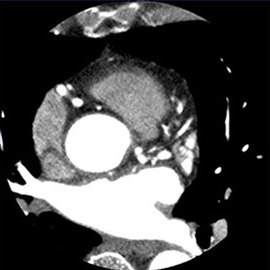

80列マルチスライスCTで撮影した画像

心臓(冠動脈)

主に狭心症や心筋梗塞などの診断